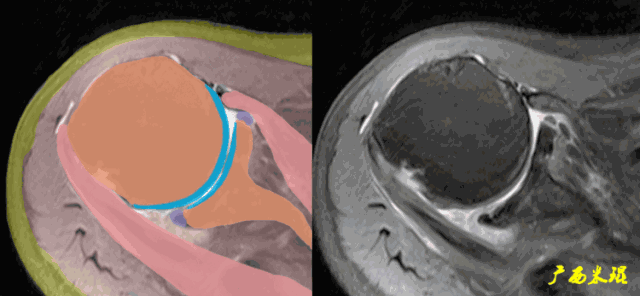

3、轴位:平行于关节盂/垂直于盂肱关节,主要评估盂唇,同时兼顾肩胛下肌、冈下肌及小圆肌。